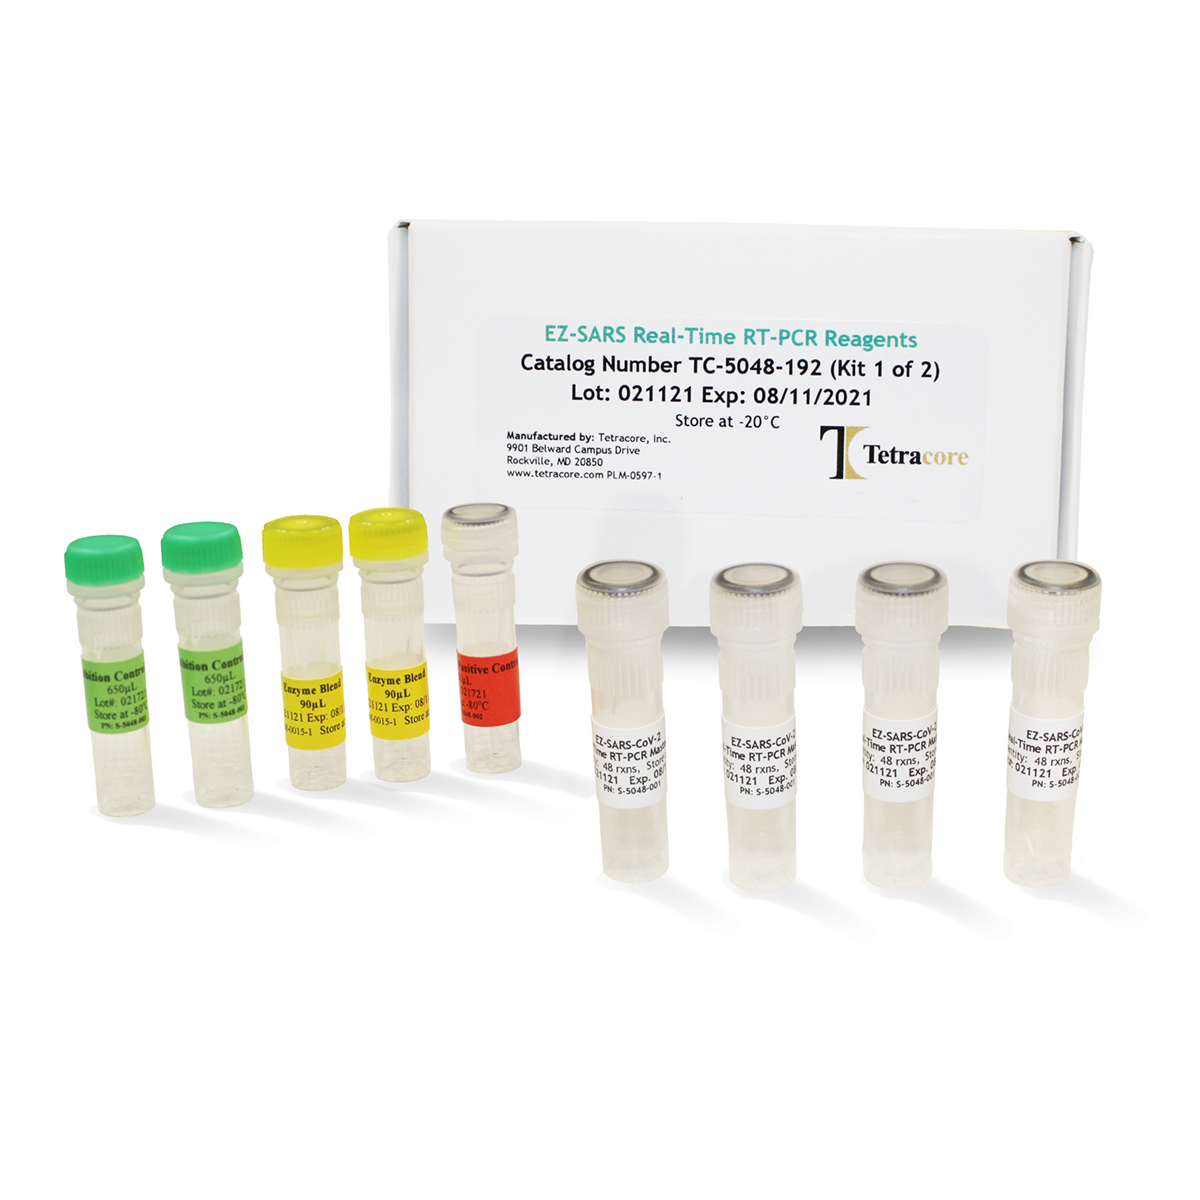

健康・医学 PCR/RT-PCRinsituLight&ElectronMicroscopy EZ-SARS-CoV-2 Real-Time RT-PCR Test - Tetracore, Inc.の詳細情報

EZ-SARS-CoV-2 Real-Time RT-PCR Test - Tetracore, Inc.。健康・医学 PCR/RT-PCRinsituLight&ElectronMicroscopy SARS-CoV。A molecular test based on RT-LAMP for rapid, sensitive and。PCR/RT- PCR in situ Light and Electron MicroscopyBy Mireille RaccurtCopyright Year 2002ISBN 9780849300417Published September 27, 2002 by CRC Press432 Pages 21 Color & 237 B/W Illustrationsご覧いただきありがとうございます。Full article: RT-LAMP in SARS-CoV-2 detection: point to。ご検討いただけますと幸いです。現時点最新版⚠️裁断済み⚠️スタンダード パーシャルデンチャー 補綴学 第4版。何卒よろしくお願いいたします。パーフェクト 人工膝関節置換術。